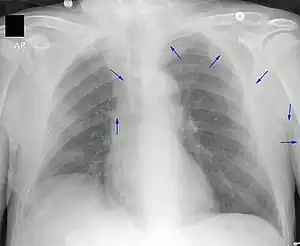

A PICC is inserted in a peripheral vein such as the cephalic vein, basilic vein or brachial vein in the arm, and then threaded through the veins toward the heart, until the end of the catheter rests in the proximal superior vena cava or cavoatrial junction. They must be inserted by a trained medical professional, including a physician, but also any trained medical professional such as a specially trained registered nurse.[8] and Interventional Radiology Technogists.[6][12] An ultrasound or chest X-ray, the use of fluoroscopy, or electrocardiography navigation can be used during insertion and to confirm placement. The insertion is a sterile procedure, but does not need to be performed in a completely sterile environment like an operating room.